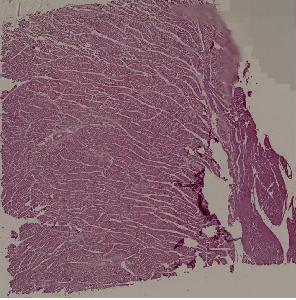

42.风湿性全心炎

高倍视野

低倍视野